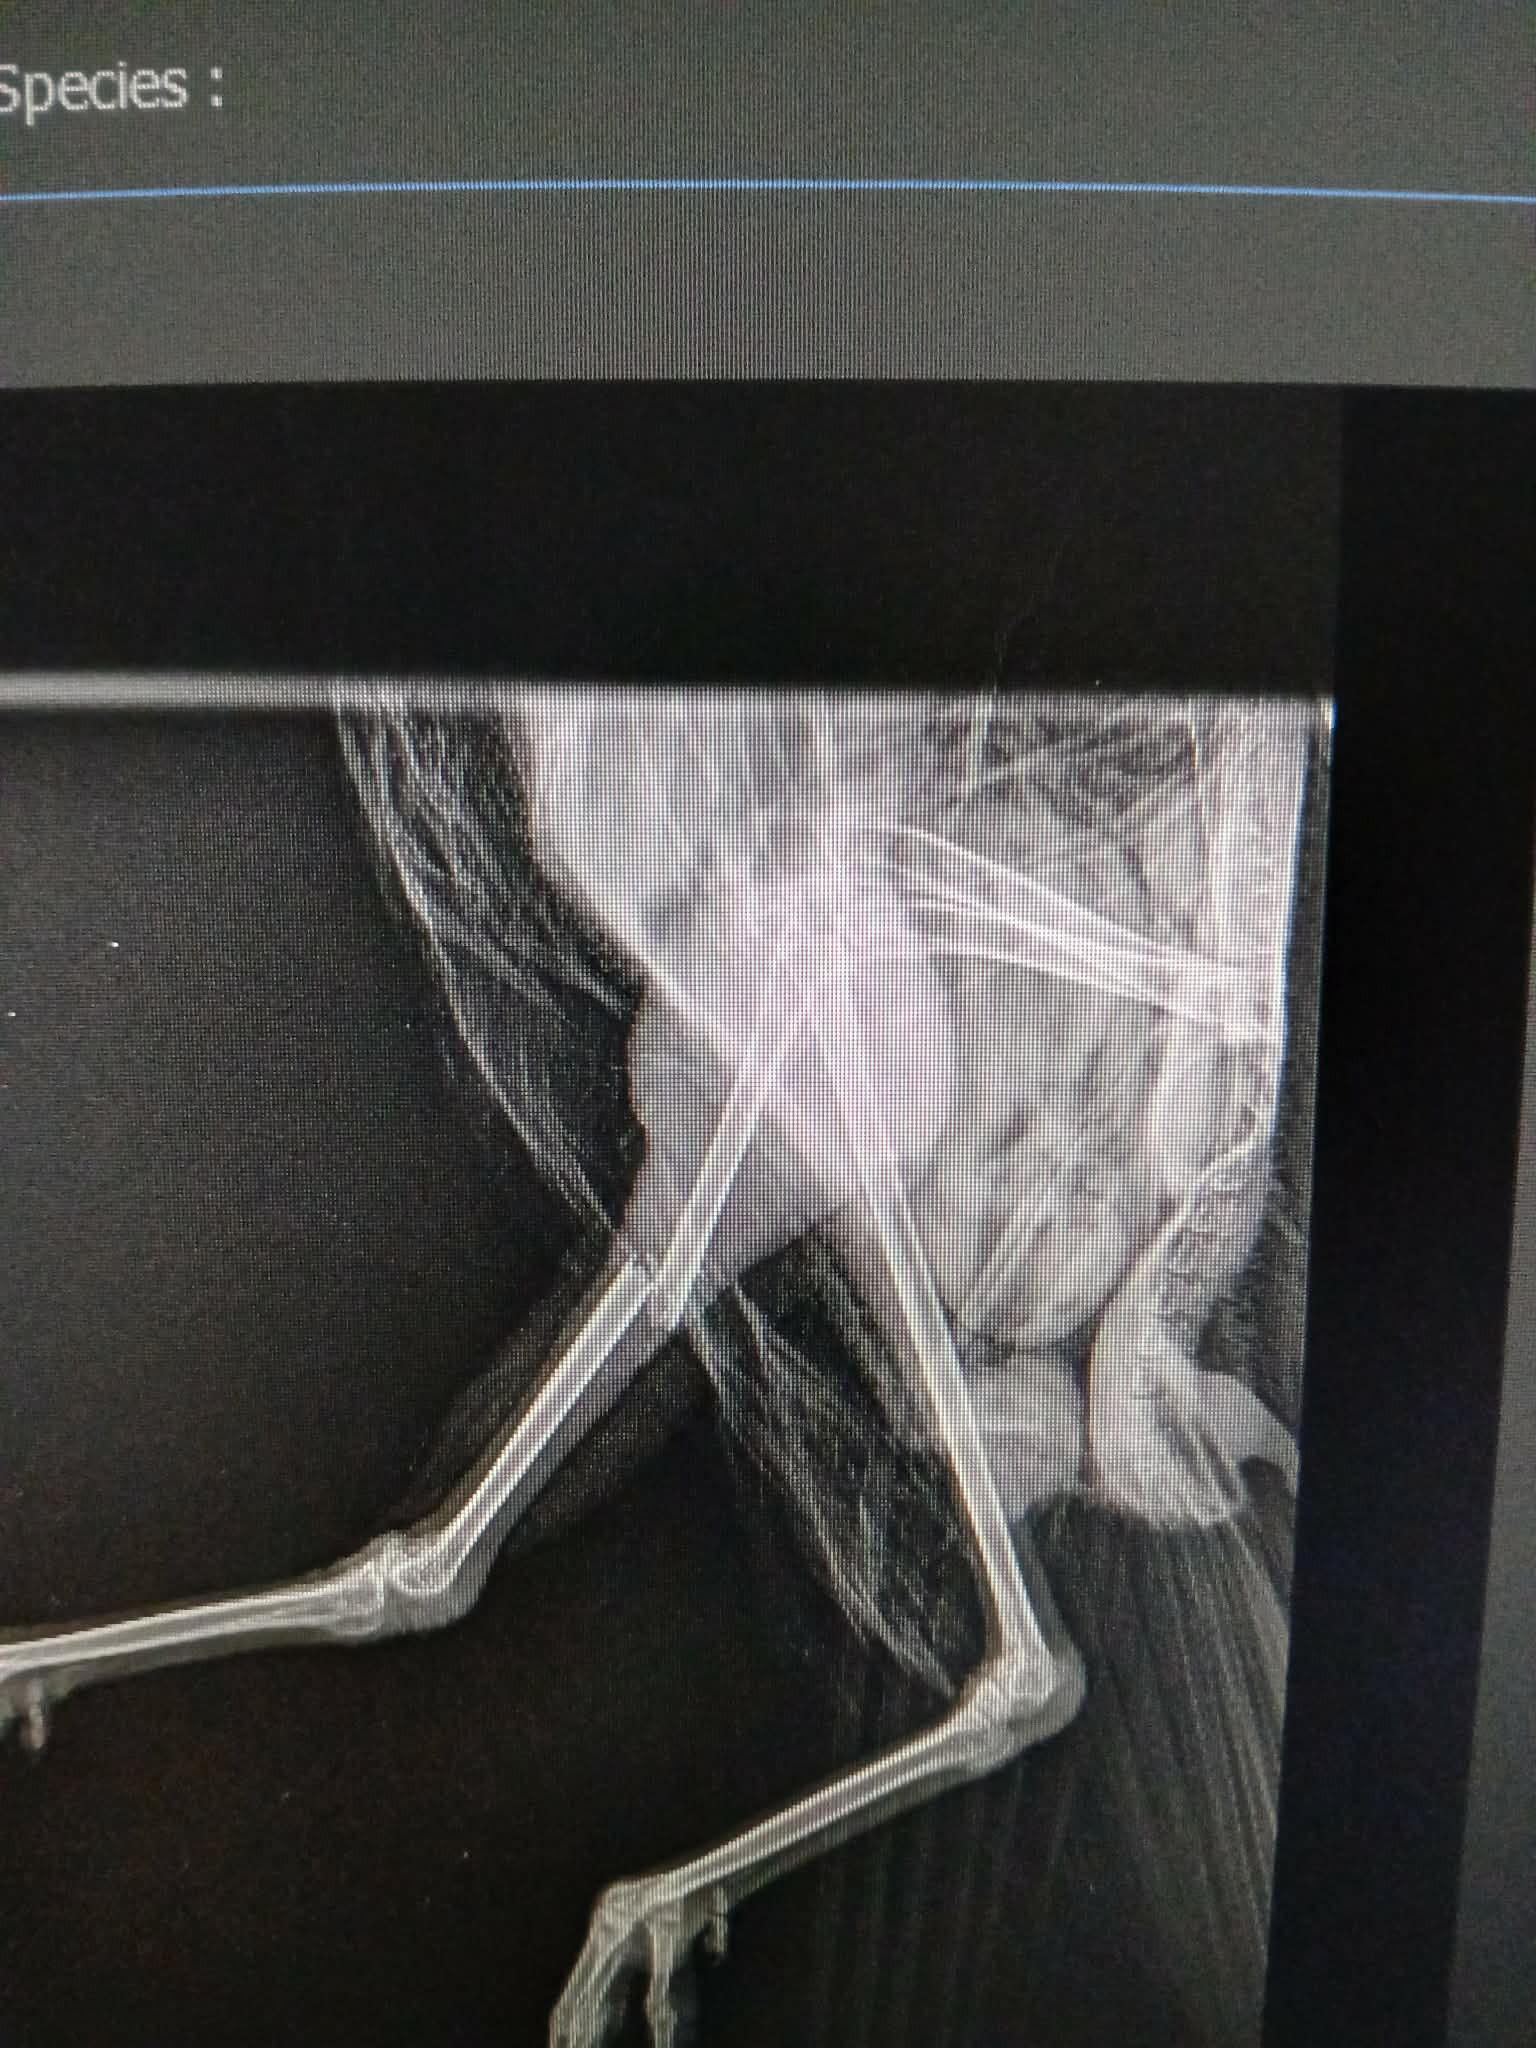

Piper was found by the side of the road near Forfar, Angus, last Thursday after a suspected hit and run. An x-ray on Friday revealed a closed fracture in his leg (mid-shaft tibiotarsus). The good news is that he’s a big, strong bird—weighing in at 1.5kg—and he’s survived the initial shock of the accident. He’s currently alert, eating well, and drinking, which gives him a really high chance of a full recovery if we can get his leg fixed.

Because it’s a clean break and hasn't pierced the skin, we've found a vet who will perform the surgery and who has given a good prognosis.

The money will cover the cost of drugs, orthopaedic implants and consumable costs. They will insert an intramedullary pin and external fixator with a second procedure to remove the implants.